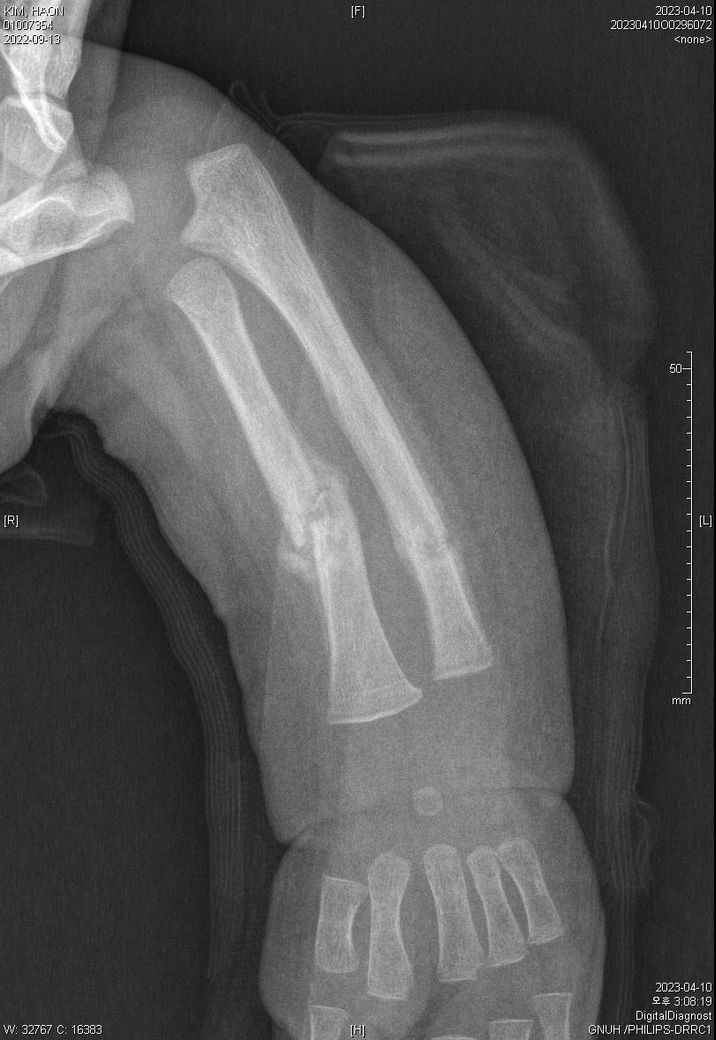

3월 30일 기준으로는 몇 일(또는 몇 주) 정도 전에 골절이 되었을 지 궁금합니다.

어떤 의사분 발언에 의하면 첨부된 4월 10일 x-ray사진처럼 유합직전의 다량의 칼러스가 발생되었다고 합니다.

아래에 3월 30일 x-ray 사진 2개, 4월 10일 X-ray 사진 2개 씩 첨부드립니다.

첨부된 사진에 X-raY 촬영 날짜가 기재되어 있습니다.

Dating fractures in infants, Clinical Radiology., Volume 66, Issue 11, November 2011, Pages 1049-1054 문헌을 보면 뚜렷한 가골 (callus)은 수상 20일쯤 확인되는걸 알 수 있습니다. 올려주신 사진을 보면 04.10에는 뚜렷한 가골이 관찰되기 때문에 20일 전인 03.20 이전일 거라고 예상이 됩니다. 03.30 X-ray에는 가골이 전혀 확인되지 않기 때문에 03.10 이후일 가능성이 높아보이고 03.10~03.20 사이가 가장 가능성이 높지 않을까 생각됩니다.